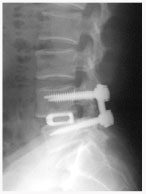

수술 방법 (Treatment)

단순 감압술 : 후방 관절의 유합없이 후방 감압만 시행

후외방 유합술(Posterlateral fusion) : 광범위한 후방 감압술 후 척추 외측에 있는 후관절과 횡돌기 간의 유합을 얻는 것.

후방 요추체간 유합술 (PLIF) : 광범위한 후방 감압술 후 추간판(디스크)을 제거한 후 골이식을 시행하여 추체간 유합을 얻는 것

전방 요추체간 유합술 (Anterior Lumbar Interbody Fusion)